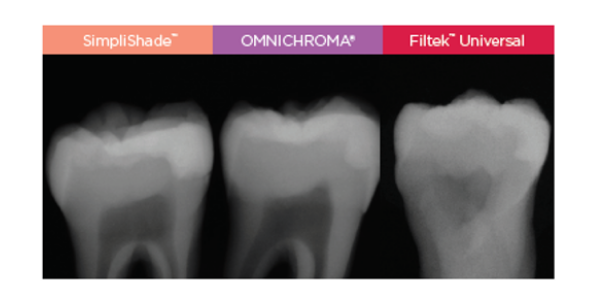

Uitstekende radiopaciteit

De hoge radiopaciteit van SimpliShade (300% AI) maakt de restauratie op een röntgenfoto zeer goed te onderscheiden van de tandstructuur.